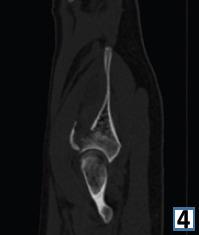

在此,我们报告一例16岁男性,有道路交通事故史,单纯闭合性左髋臼骨折。X线显示双侧髋臼柱骨折伴中心性半脱位。通过改良的Stoppa入路并带有外侧窗口对其进行切开复位内固定治疗。患者在受伤后第6天接受了ORIF。使用钢板和螺钉进行固定。在恢复室,他整个左上肢无法活动且无感觉,而手术肢体的远端神经血管功能正常。恢复15分钟后,感觉恢复,但运动功能障碍持续存在,提示臂丛神经失用。进行了脑部CT扫描,结果未见异常。6个月后,患者自行恢复了感觉,左上肢力量改善至5/5。